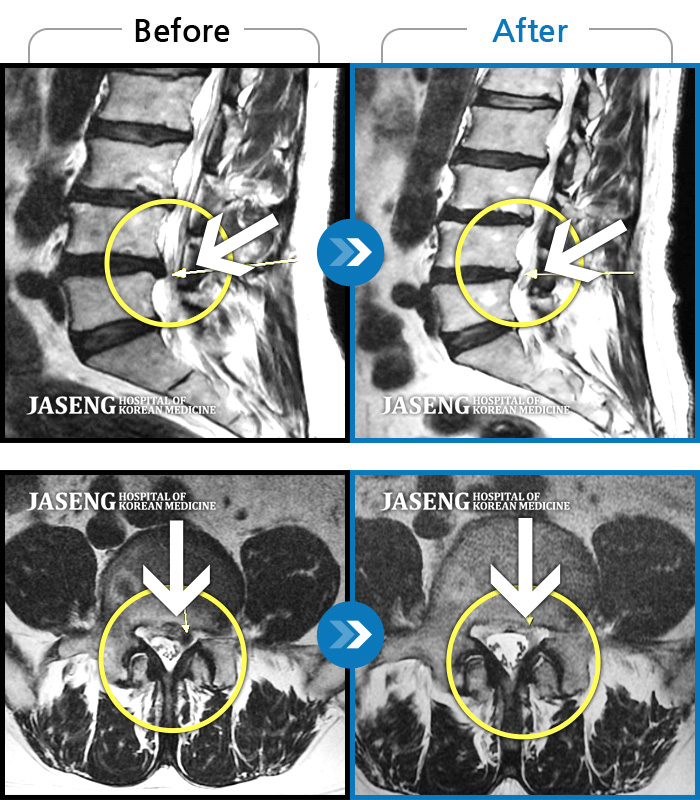

허리디스크

울산 · 정운석 원장

좌측 하지 외측이 저리면서 당김증상 및 감각둔화

촬영시기

2016.12.22 ~ 2022.11.24

2022.12.09